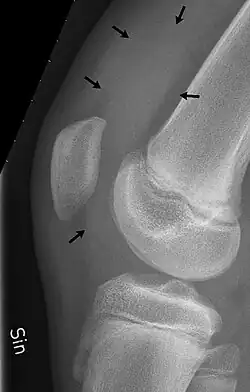

Traumatic effusion of the right knee, with swelling lateral to the kneecap marked by an arrow | |

X-Ray

An X-ray may be recommended by your provider as a way to obtain a 2-dimensional image to visualize the joint in question. In the presence of trauma an X-ray can be especially useful to verify that there is no break, dislocation, or deformity. In an atraumatic knee, an X-Ray can be used to identify or rule out other causes of a knee infusion including some inflammatory or age-related causes.